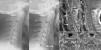

Nontraumatic emergencies of the head and neck represent a challenge in the field of neuroradiology for two reasons. As explained in the first part of this update, these entities affect an area where the thorax joins the cranial cavity and can thus compromise both structures; second, they are uncommon, so they are not well known.

Maintaining the same approach as in the first part, focusing on the clinical presentations in the emergency department rather than on the anatomic regions affected, we will study the entities that present with two patterns: those that present with a combination of cervical numbness, dysphagia, and dyspnoea and those that present with acute sensory deficits. In the latter group, we will specifically focus on visual deficits, because this is the most common symptom that calls for urgent imaging studies.